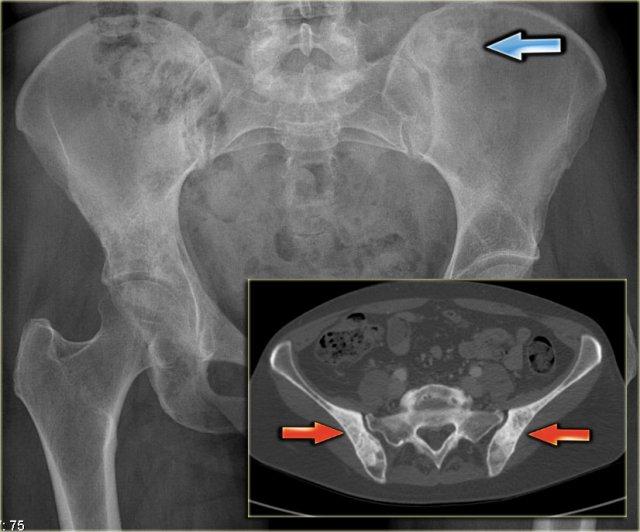

Đây là hình chụp X-quang vùng chậu với một ổ di căn tạo xương hầu như không nhìn thấy ở xương chậu trái (mũi tên xanh lam).

Lưu ý rằng CT mô tả các tổn thương này rõ hơn nhiều (mũi tên đỏ).

Đây là hình ảnh CT của một bệnh nhân ung thư tuyến tiền liệt.

Lưu ý các di căn tạo xương không rõ ranh giới lan rộng.